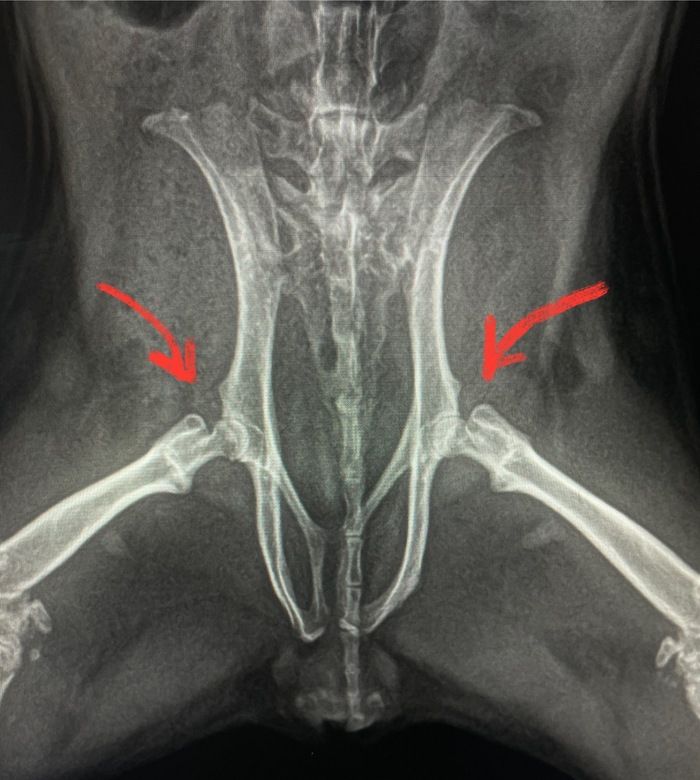

Прошло три недели. Сделали повторный рентген.

На радость всем, по костям пошли маленькие, но улучшения. Ноги остаются при свинке)

Оба с владельцем понимаем, что нужен рентген, и вновь он решающий. На лучшее я уже не надеюсь и морально готовилюсь сообщить плохие новости.

Заношу данные пациента в программу, выставляю параметры рентгена, фиксируем недовольную свинку. Щёлк, щёлк. Отдаю свинку ассистенту и напряжённо подхожу к компьютеру, чтобы рассмотреть снимки. Удивленно поднимаю брови.

- А неплохо, очень неплохо. Даже хорошо. Далеко не идеально, но для этого пациента вообще прекрасная динамика.